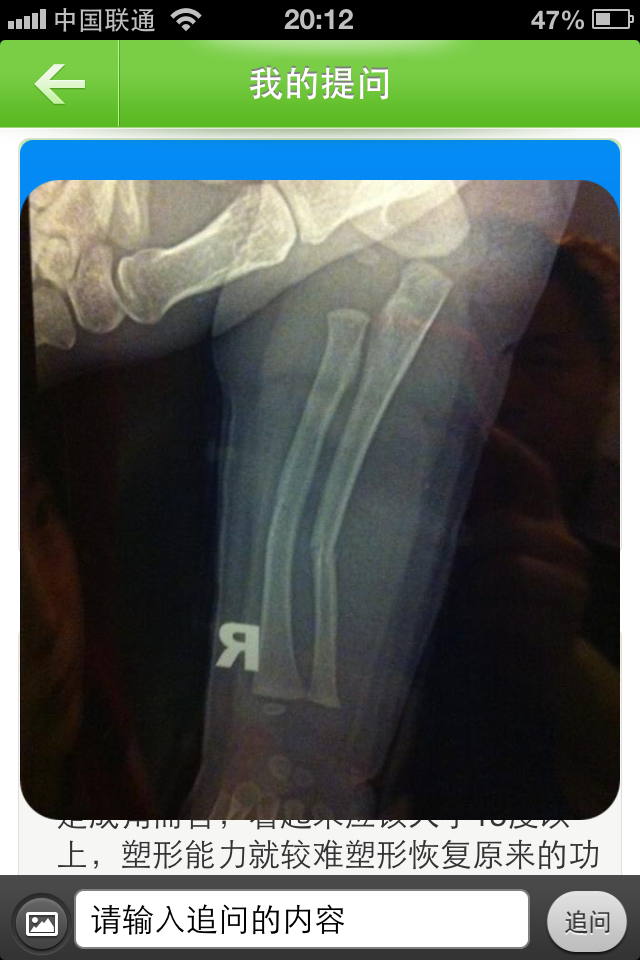

患者信息:女 1岁 吉林 吉林 病情描述(发病时间、主要症状等):6天前去看医生没发现骨折以为是脱臼了 就给按脱臼治的 因为过了这几天她还有些疼就心思领她去看看 今天去看才发现左手臂中段骨折 有弯曲 比较严重 所以 找了大夫给做了下牵引复位 宝宝太遭罪了 复位后 虽然手臂基本直了 但是其中一个骨头比之前断的严重了 手臂已经用夹板固定上了不知道这样行不行 能不能慢慢恢复想得到怎样的帮助:手法复位现在的效果不知道行不行 谁帮看看 能不能恢复好 真是揪心啊 片子带出去给人看了先看个之前照到 求求大家帮先看一下

我想看看复位后的 看这个 复位后的应该可以 才1岁 首先这样的骨折不需要解剖复位 因为孩子成长特别快 有错位也会在成长中自行朔型 就算这个是复位后的片子 孩子活动也不会受影响 但是外形受影响 看起来畸形 不过随着成长 在10岁前就可以朔型几乎正常 夹板固定是必要的 因为孩子不可能老实的养伤 防止继续...错位 必要的固定是必须的 复位完的片子比这个好就最好了 不能手术 髄内针可能破坏骨骺 影响生长 再说手术对孩子的痛苦可想而知 所以 复位时牵引尺骨 轻按挠骨的弧形突出让对线更好些 就比较完美了

这个尺骨中远端骨折,成角较大,应该考虑打入内固定钢针,否则有残废可能。 夹板固定不可取,,牵引就更不可取了。